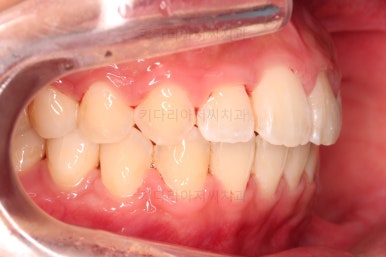

1. 초진 시 입안의 모습 평가

부산연산역치아교정 키다리아저씨치과에 처음 내원했을 당시의 입안의 모습이비다.

앞니 약간, 어금니쪽 약간 삐뚤어진 것, 그리고 위아래 앞니가 약간 뻗쳐 보이는 양상 이외에는 매우 가지런해 보여서 교정치료를 굳이 왜 하시려고 하지? 라고 생각될 정도의 치열 상태였습니다.